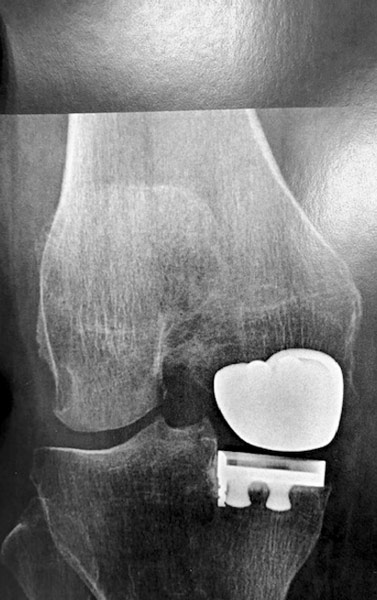

Homme 60 ans, opéré par prothèse rotulienne et prothèse uni-compartimentale interne. Toujours douloureux.

Pas d’infection.

Changement pour mettre en place une prothèse totale du genou. Aucune douleur résiduelle.